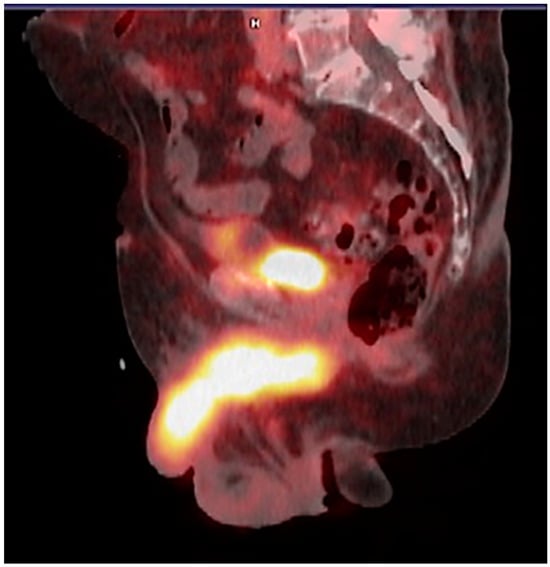

3.2. Diagnosis with PET/CT with 18F-Fluoride